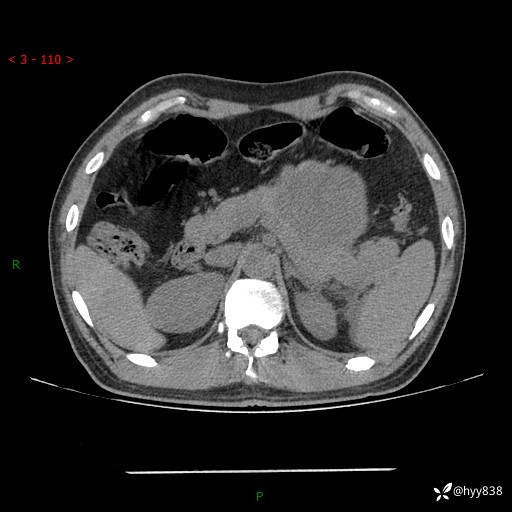

病例39岁/女,左侧腰痛入院。腹腔囊实性肿块,定位、定性---结果公布~

性别:男

年龄:39岁

简要病史:左侧腰痛待查,CT发现腹腔占位

腹部CT平扫+增强